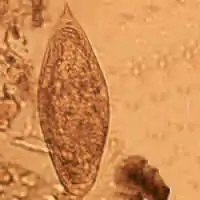

| Schistosoma mansoni egg | |